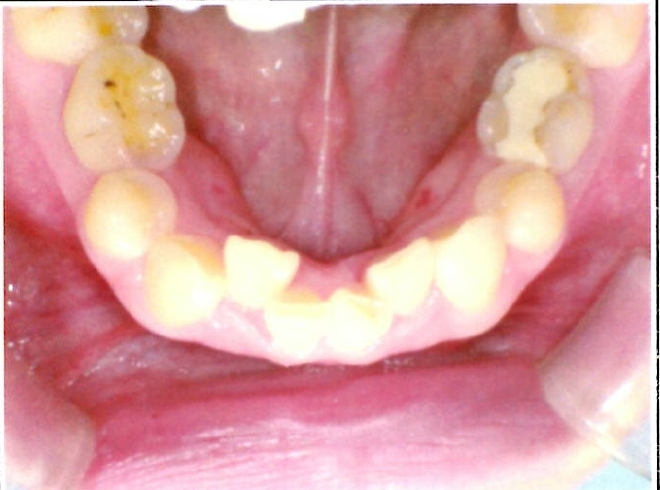

| 主訴・治療前の状態 | 下顎前歯部に叢生(ガタガタ)があり、歯ブラシが届きにくく清掃性に問題がありました。また、見た目も気にされていました。 |

| 治療内容 | 下顎前歯を1本のみ抜歯し、歯列を整えました。治療に際しては、ブラックトライアングル(歯と歯の間の歯茎部分に三角形の隙間ができること)が生じる可能性について事前に説明し、患者様にご了承いただいた上で治療を開始しました。 |

| 治療結果 | 予定通りの仕上がりとなり、事前説明の通りブラックトライアングルは生じましたが、患者様には十分ご理解いただいており、満足度の高い結果となりました。 |